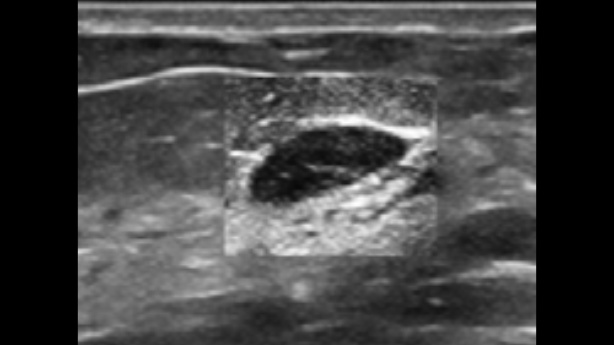

EcĂłgrafo Zeus presenta una interfaz fĂĄcil de usar y funciones sencillas para realizar exploraciones eficientes. Sus versĂĄtiles capacidades abarcan la ecografĂa abdominal, vascular, de partes peque?as y musculoesquelĂ©tica, lo que aumenta la confianza en el diagnĂłstico.